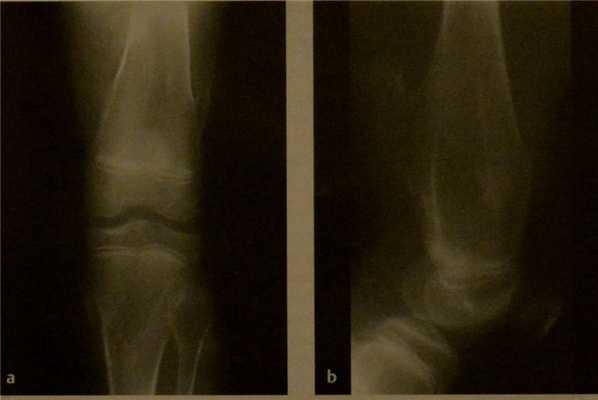

Остеохондрома. Рентгенограмма коленного сустава в 2 плоскостях. Множественные остеохондромы метафиза, преимущественно на широком основании. Метафизы расширены и утолщены.